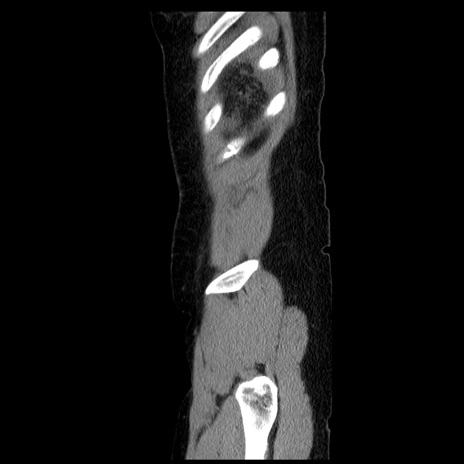

症例6(矢状断像)

【症例】50歳代女性

【主訴】下腹部痛

【現病歴】本日朝より下痢2回あり。 昼食を食べた後、嘔吐3回、下腹部痛認め、症状軽快せず、当院救急搬送。

最終食事:本日昼(生ものなし)。 昨日の夜、刺身を食ぺたとのこと。周囲に同様の症状の者なし。普段、排便は毎日あるとのこと。

【既往歴】卵巣癌術後(8年前に当院で卵巣摘出)

【身体所見】 意識清明、腹部:平坦、腸蠕動音→、やや硬、下腹部自発痛・圧痛あり、反跳痛あり、筋性防御なし。

【データ】WBC 16000、CRP 0.01